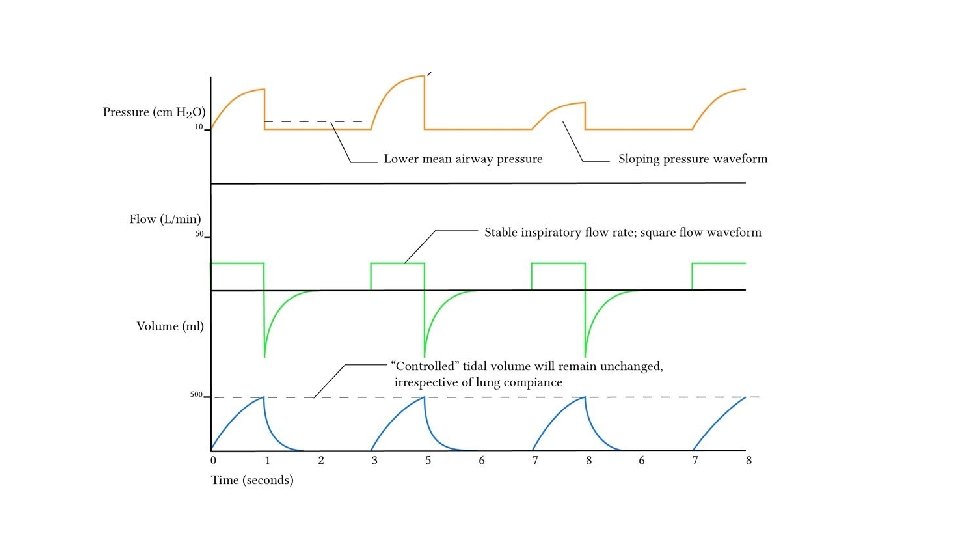

Ventilator Modes Volume Control Ventilation Favours the control of ventilation Advantages Disadvantages Guaranteed VT produces more reliable MV Mean airway pressure is lower MV remains stable despite changing lung dynamics Recruitment may be poorer in lung units with poor compliance Initial flow rate is lower than in PCV (avoids resistance related early peak pressure) In the presence of a leak, the mean airway pressure maybe unstable